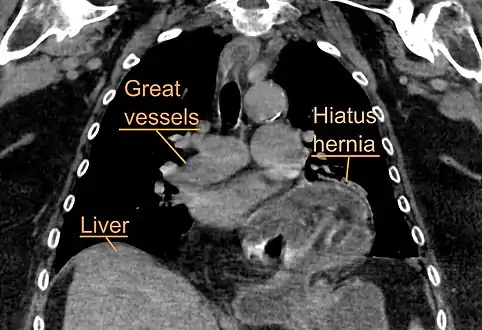

The diagnosis of a hiatal hernia is typically made through an upper GI series, endoscopy, high resolution manometry, esophageal pH monitoring, and computed tomography (CT). Barium swallow as in upper GI series allows the size, location, stricture, stenosis of oesophagus to be seen. It can also evaluate the oesophageal movements. Endoscopy can analyse the esophageal internal surface for erosions, ulcers, and tumours. Meanwhile, manometry can determine the integrity of esophageal movements, and the presence of esophageal achalasia. pH testings allows the quantitative analysis of acid reflux episodes. CT scan is useful in diagnosing complications of hiatal hernia such as gastric volvulus, perforation, pneumoperitoneum, and pneumomediastinum.[8]

Type IV: Type IV hiatus hernia is associated with a large defect in the phrenoesophageal ligament, allowing other organs, such as colon, spleen, pancreas and small intestine to enter the hernia sac.